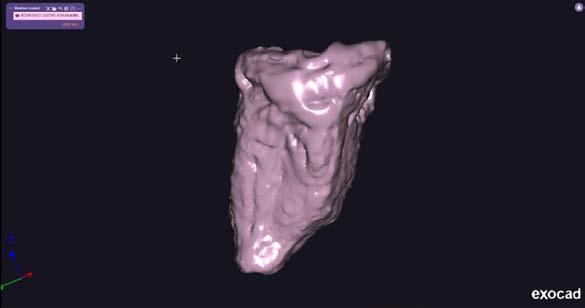

44 | CASO CLÍNICO

Autotrasplante de terceros molares mediante el uso de una guía de impresión tridimensional: Revisión de la literatura y reporte de un caso clínico